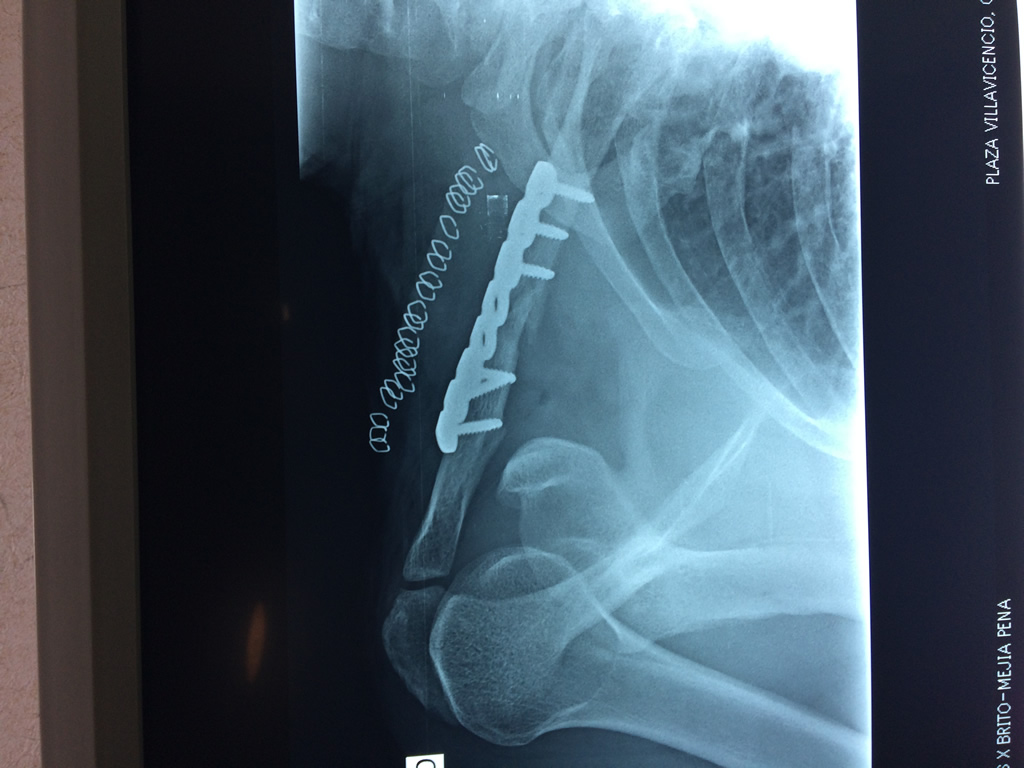

Cirugías de Codos - Clavícula

La clavícula es un hueso largo, con forma de "S" itálica, situado en la parte anterosuperior del tórax. Junto con la escápula forman la cintura escapular. Se puede palpar por toda su longitud y se extiende del esternón al acromion de la escápula, siguiendo una dirección oblicua lateral y posterior.